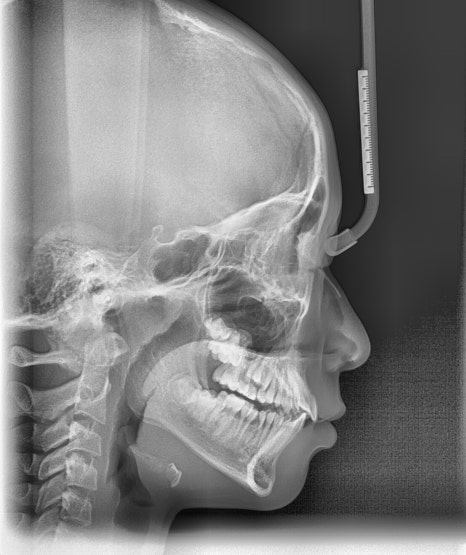

본 환자는 앞니가 점점 돌출된다는 주소로 치과에 내원하였으며, 앞니가 많이 뻗쳐있었고 과개교합 양상도 보였습니다. 또한 어금니 위치 관계도 2급(아래 어금니가 뒤로 후퇴하여 물리는 위치 관계) 이었습니다.

2024.8.3. 초진

편안하게 입술을 다물었을 때 후퇴된 아래턱 및 돌출된 위 앞니가 하순에 닿아 눌러서 아래턱은 후퇴되어 있음에도 아래 입술은 오히려 돌출감이 있었습니다.

약 9개월간 2급 액티베이터와 헤드기어 착용 후 모습입니다.

2025.5.16.

치료 전후 악골의 위치 변화

치료 결과 하악골은 전방성장하였으며, 과개교합도 많이 개선되었습니다. 헤드기어로 상악골의 성장도 억제되어 돌출되었던 위 앞니 각도도 개선되었고, 위-아래 앞니 사이 간격이 많이 줄었습니다. 위 앞니에 눌려 돌출되었던 하순도 개선되어 straight profile이 완성되었습니다.